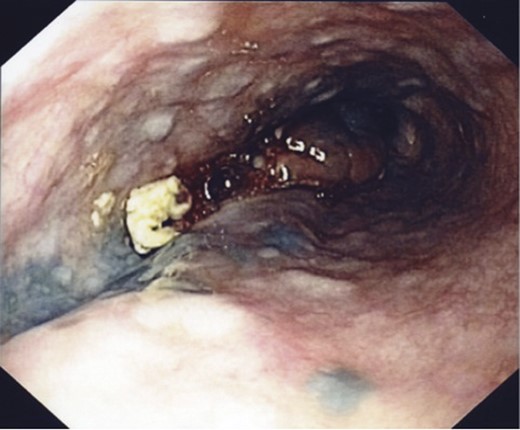

His initial endoscopy showed a 12 cm fungating, pigmented tumour occupying most of lower oesophageal lumen (Fig. 1). The biopsy was highly suggestive of primary malignant melanoma. Staging computed tomography (CT) and positron emission tomography (PET) showed extensive mediastinal, left supraclavicular and coeliac lymph node enlargement (FDG avid) with no evidence of metastatic disease (Fig. 2).

An endoscopic view of the fungating melanoma involving most of the oesophageal lumen.